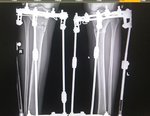

Дата операции 05.04.2016г.

Дата снятия аппаратов 05.07.2016г.

Срок лечения 90 дней.